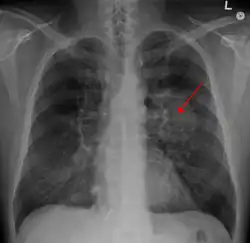

| A chest X-ray showing a tumor in the lung (marked by arrow) | |

A person suspected of having lung cancer will have imaging tests done to evaluate the presence, extent, and location of tumors. First, many primary care providers perform a chest X-ray to look for a mass inside the lung.[9] The X-ray may reveal an obvious mass, the widening of the mediastinum (suggestive of spread to lymph nodes there), atelectasis (lung collapse), consolidation (pneumonia), or pleural effusion;[10] however, some lung tumors are not visible by X-ray.[6] Next, many undergo computed tomography (CT) scanning, which can reveal the sizes and locations of tumors.[9][11]